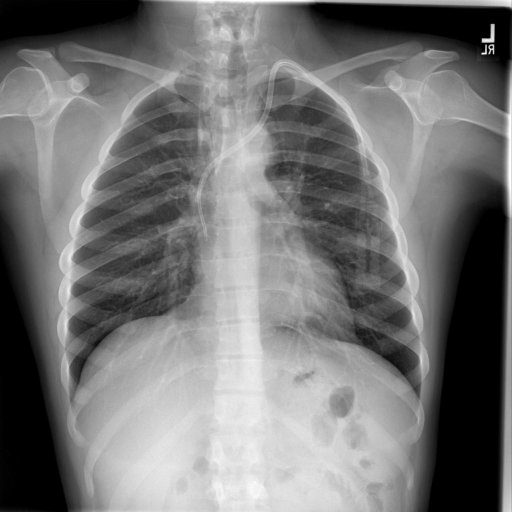

For the disease multi-class classification we used the ViTLLaMAII, as already done by [9], and additionally trained a ResNetLLAMAII, a ViTMLP and a ResNetMLP. The task’s goal is to detect diseases regarding the lung using image–text pairs. Following [9, 12], the 3,677 image–text data-pairs were split with 87:3:10 into training (3,199), validation (101) and testing (377) datasets.

4.1.2 Dataset

The image–text dataset from Open I [1] contains 2D Chest X-Rays together with a clinical report for each patient (see Fig.˜1). We used data from 3,677 patients the same way as done in [12]. In addition, we removed the class labels from the text. The 14 target classes include twelve diseases regarding the chest, especially the lungs (i.e. atelectasis, cardiomegaly, consolidation, edema, enlarged cardiomediastinum, fracture, lung lesion, lung opacity, pleural effusion, pleural other, pneumonia, pneumothorax), one for support devices and one for no finding.

FINDINGS : The heart is normal in size. The mediastinum is within normal limits. Pectus deformity is noted. Left IJ dual-lumen catheter is visualized without pneumothorax. The lungs are clear. IMPRESSION : No acute disease.